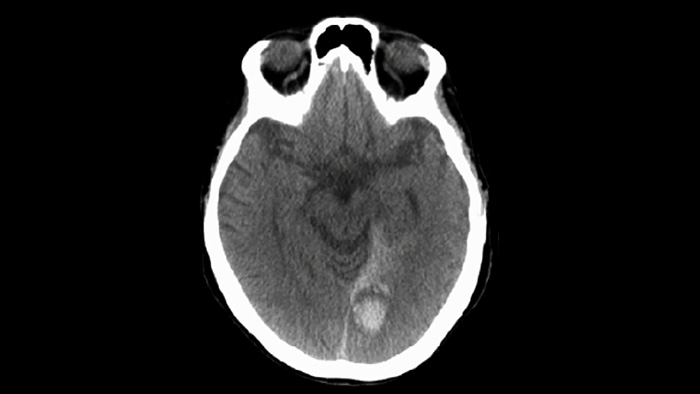

Utilisez l’imagerie SmartCT Soft Tissue dans la suite neurovasculaire pour vérifier la réussite du traitement et identifier les hémorragies.